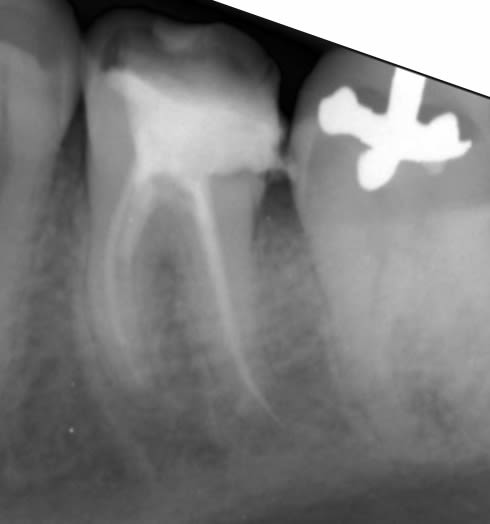

On fait quoi?

On fait quoi lu1sts - Eugenol

Symptomatique?

je te le dis dans 20 min ;-) la patiente arrive.

asympto, je surveille tous les 6 mois. Un jour faudra peut être faire quelque chose.

La prov est scellée au polycarboxylates, donc étanche.

Je me connais, si elle se descellait, je tenterais une CR avec un moignon compo probablement.

L'implant c'est la facilité...

On sent bien la French touch, en plus c'était pas du low-coast!!

Peut être que le confrère qui a mis le tenon, n'était pas le même que celui qui a posé le screw post ?

Bien vu. Le tenon, c'est pas le souci, tu supprimes le surplomb en Ml, ça redresse l'axe et ... et quoi au fait?-)

Le screw c'est chiant, asympto depuis 15 à 20 ans effectivement.

Perso, je surveille l'espace inter radiculaire et j'attends que ça se descelle... qu'il se passe quelque chose.

je pense reconnaître la même philosophie de soins sur la 45, j'espère pas y toucher:-))

Si ya pas de perfo en regard du screw post je m'en coupe une.

Nan pas fait, c'est asympto et ça changerait rien de faire un 3D (voir les recommandations, la prescription d'un 3D doit apporter un bénéfice, là y a pas)... on le saura le jour le l'autopsie:-)

Personne est pour déposer le screw, bourrer au MTA, rte, IC, CR:-))